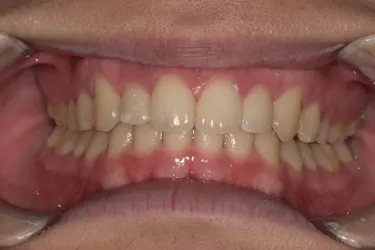

歯並びがコンプレックスで友人と写真を撮る際も気にしてしまっていたという20歳の男子大学生I.T.様にのI.T.様。始めやすい価格と目立ちにくさからスマイルモア矯正を選び、自信を持って笑えるようになった経緯を伺いました。

長年、自分の歯並びにコンプレックスがあり、友人と写真を撮るときもいつも歯並びを気にしてしまっていたんです。自信を持って笑えないことが一番の悩みでした。 この悩みを解消し、将来的な歯や口の健康も考えて、矯正を始めようと思いました。

本当にやって良かったの一言です。 長年のコンプレックスだった歯並びが整い、今は自信を持って笑えるようになりました。 矯正中は間食しにくいなどの不便もありましたが、慣れてしまえば負担には感じず、むしろ生活習慣の改善にもつながりました。 仕上がりを鏡で見るたびに嬉しくなり、思い切って始めて良かったと心から思います!